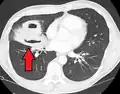

Lung abscesses are often on one side and single involving posterior segments of the upper lobes and the apical segments of the lower lobes as these areas are gravity dependent when lying down. Presence of air-fluid levels implies rupture into the bronchial tree or rarely growth of gas forming organism.

Pulmonary abscess on CT scan -